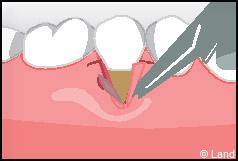

LES TECHNIQUES SANS APPORT DE GENCIVE :

Elles font appel à des lambeaux de gencive restante à proximité des récessions, qui sont déplacés et repositionnés sur la récession.